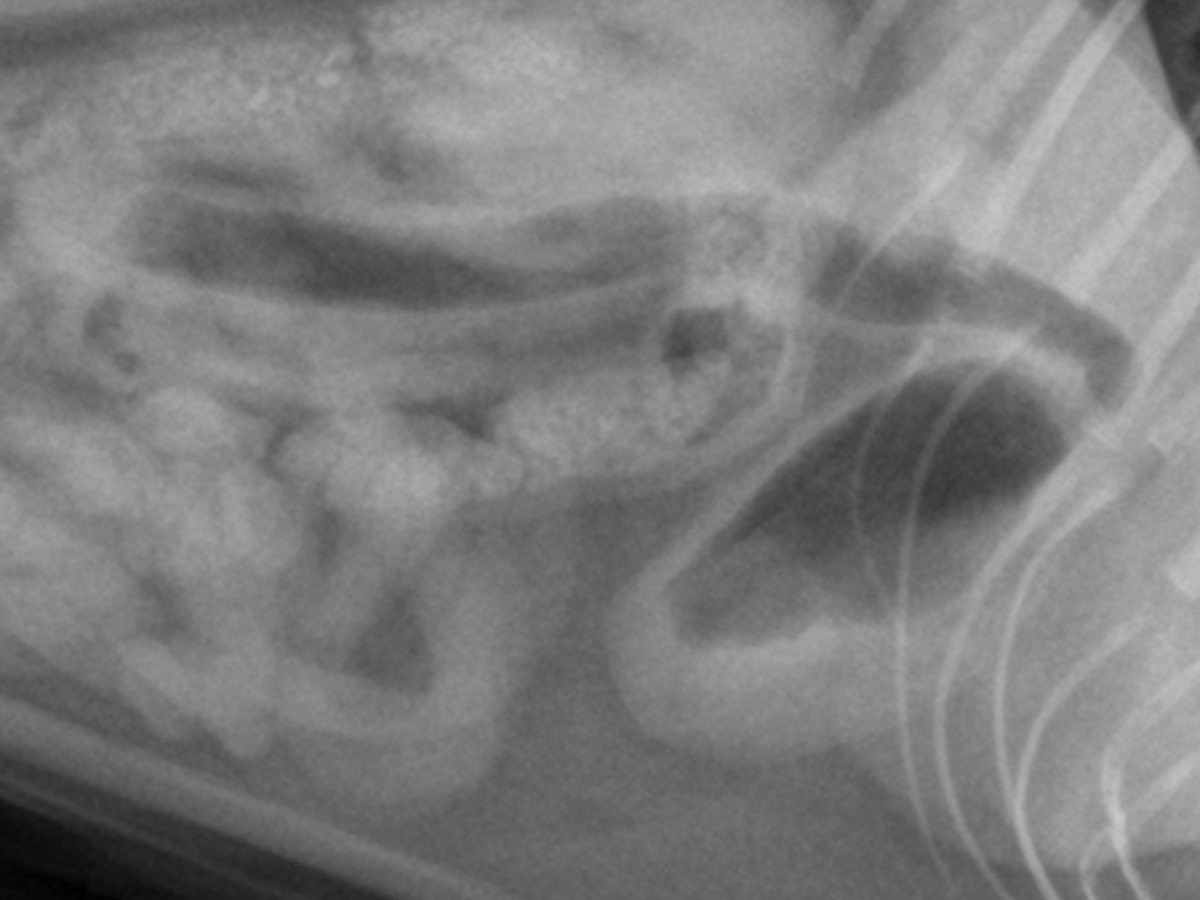

mijn kater Balim moet met spoed geopareerd worden maar de kosten zijn super hoog. Wil je ons een steentje bijdragen?